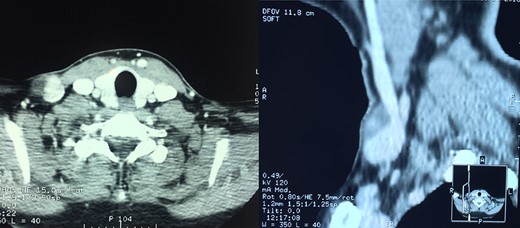

A CT angiography revealed a 1.6 × 2.1 cm sized venous aneurysm with intraluminal thrombus (Fig. 2) to prevent a possible pulmonary embolism, surgical excision is indicated.

Axial and coronal multidetector CT images following intravenous contrast administration showing the saccular aneurysm arising from the external jugular vein.